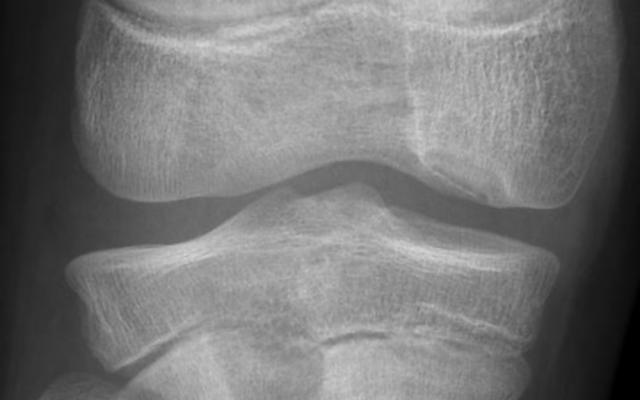

Dit artikel is alleen beschikbaar als PDF.Lees de PDF Artikelinformatie 7 januari 1862 Citeer dit artikel als Ned Tijdschr Geneeskd. 1862;6:33-6 Heb je nog vragen na het lezen van dit artikel? Check onze AI-tool en verbaas je over de antwoorden. ASK NTVG Ook interessant Casuïstiek Breuken van doornuitsteeksels door indirect geweld Nieuws Betere preoperatieve differentiatie tussen directe en indirecte liesbreuk Beeldquiz Pijn in de knieholte Meer gerelateerd … Reacties Login om een reactie te plaatsen